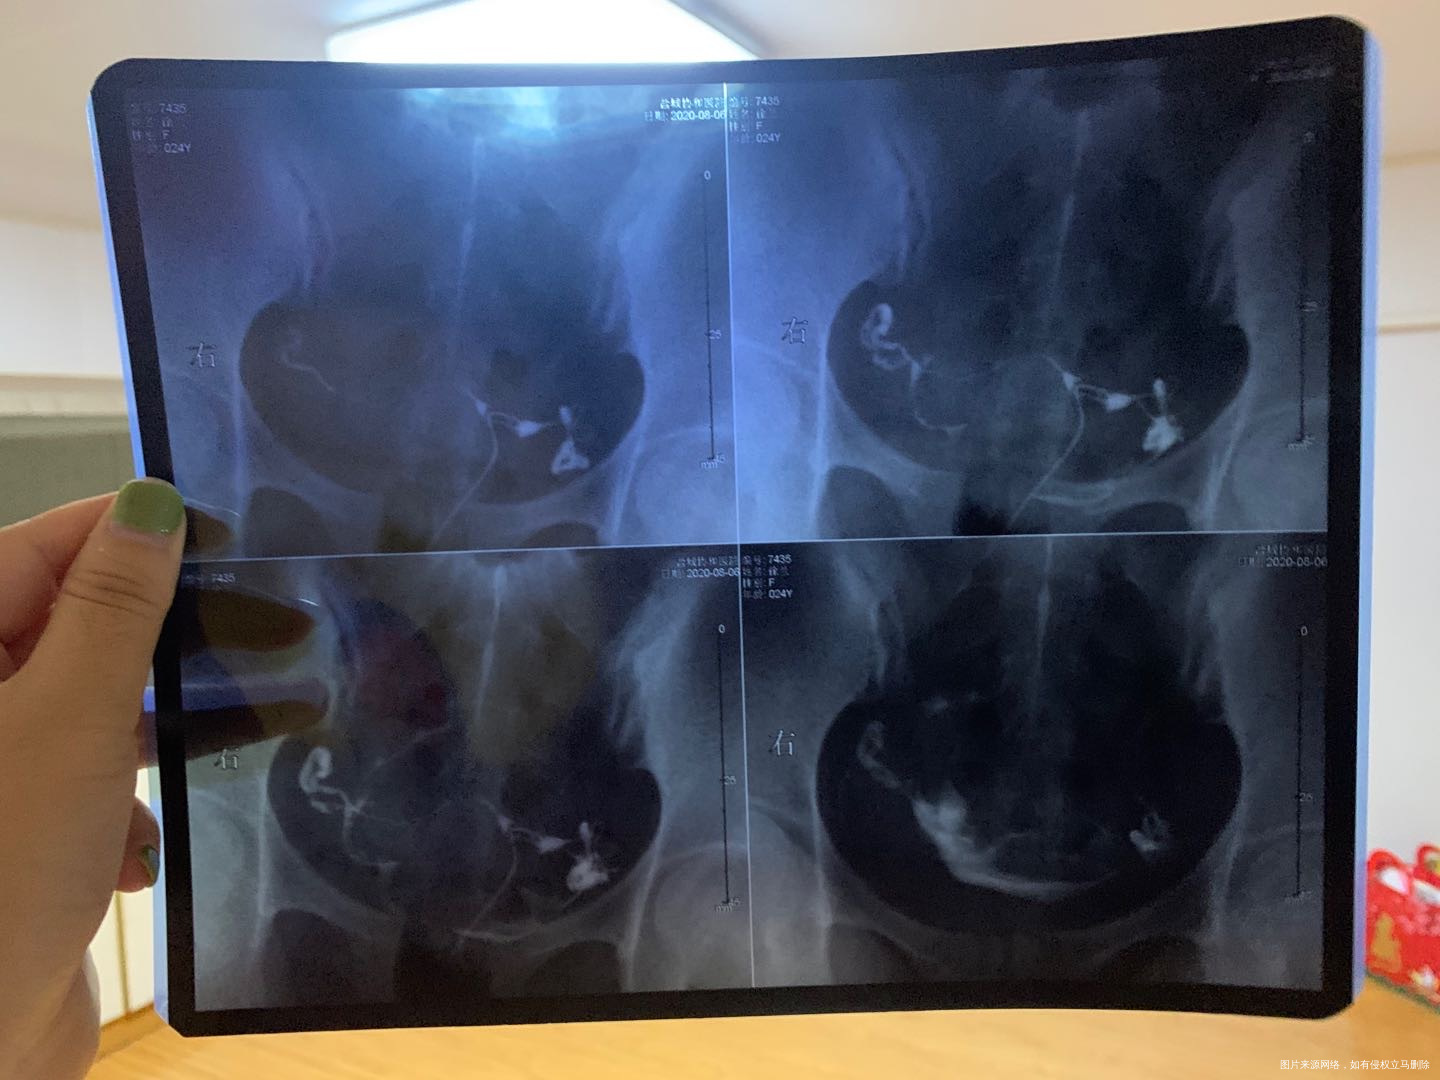

请问一下我这样情况输卵管算严重的嘛?我没怀过孕也没打过胎,就支原体阳性有了两年,之前没结婚就一直没治疗过,不知道是不是这个原因导致我输卵管不好,这样是建议治疗还是直接试管呢?谢谢🙏

不是支原体阳性引起的,可以做输卵管通液,术后予以灌肠红外线等治疗,这样可以使输卵管通畅的,不行可以做导丝疏通输卵管的。术后2个月就可以备孕的,排卵期增加同房次数,提高怀孕机率。放松心情,一年内怀孕是正常的。

小幸運 回复 姬晓丽:我这个算是积水嘛右侧?有医生说让我做导丝,有医生说让我别治疗,有医生说吃三个月中药消炎,不知道咋办好了

孙星宇

您好,目前您这个情况最好的就是做腹腔镜。输卵管积液一般是指输卵管受病原体感染以后,由于白细胞的浸润形成内膜肿胀、间质水肿、渗出,输卵管粘膜上皮脱落导致,简单来说就是炎症,不建议做导丝。如果您不想做手术可以考虑用中药。反正最主要的就是治疗慢性盆腔炎。

输卵管有问题和有没有怀过孕打过胎或支原体感染没有必然的关系,一般都是因为输卵管炎症导致的输卵管通而不畅,和之前有过附件炎或盆腔炎没有正规治疗有关系。如果有备孕需求,可以在造影后第二个月正常备孕,输卵管造影有一定的疏通输卵管的作用,一般做完造影前半年有一定的怀孕几率。假如一年怀不上,建议做试管。做手术意义不大,可能很快就粘连上,另外有可能宫外孕。